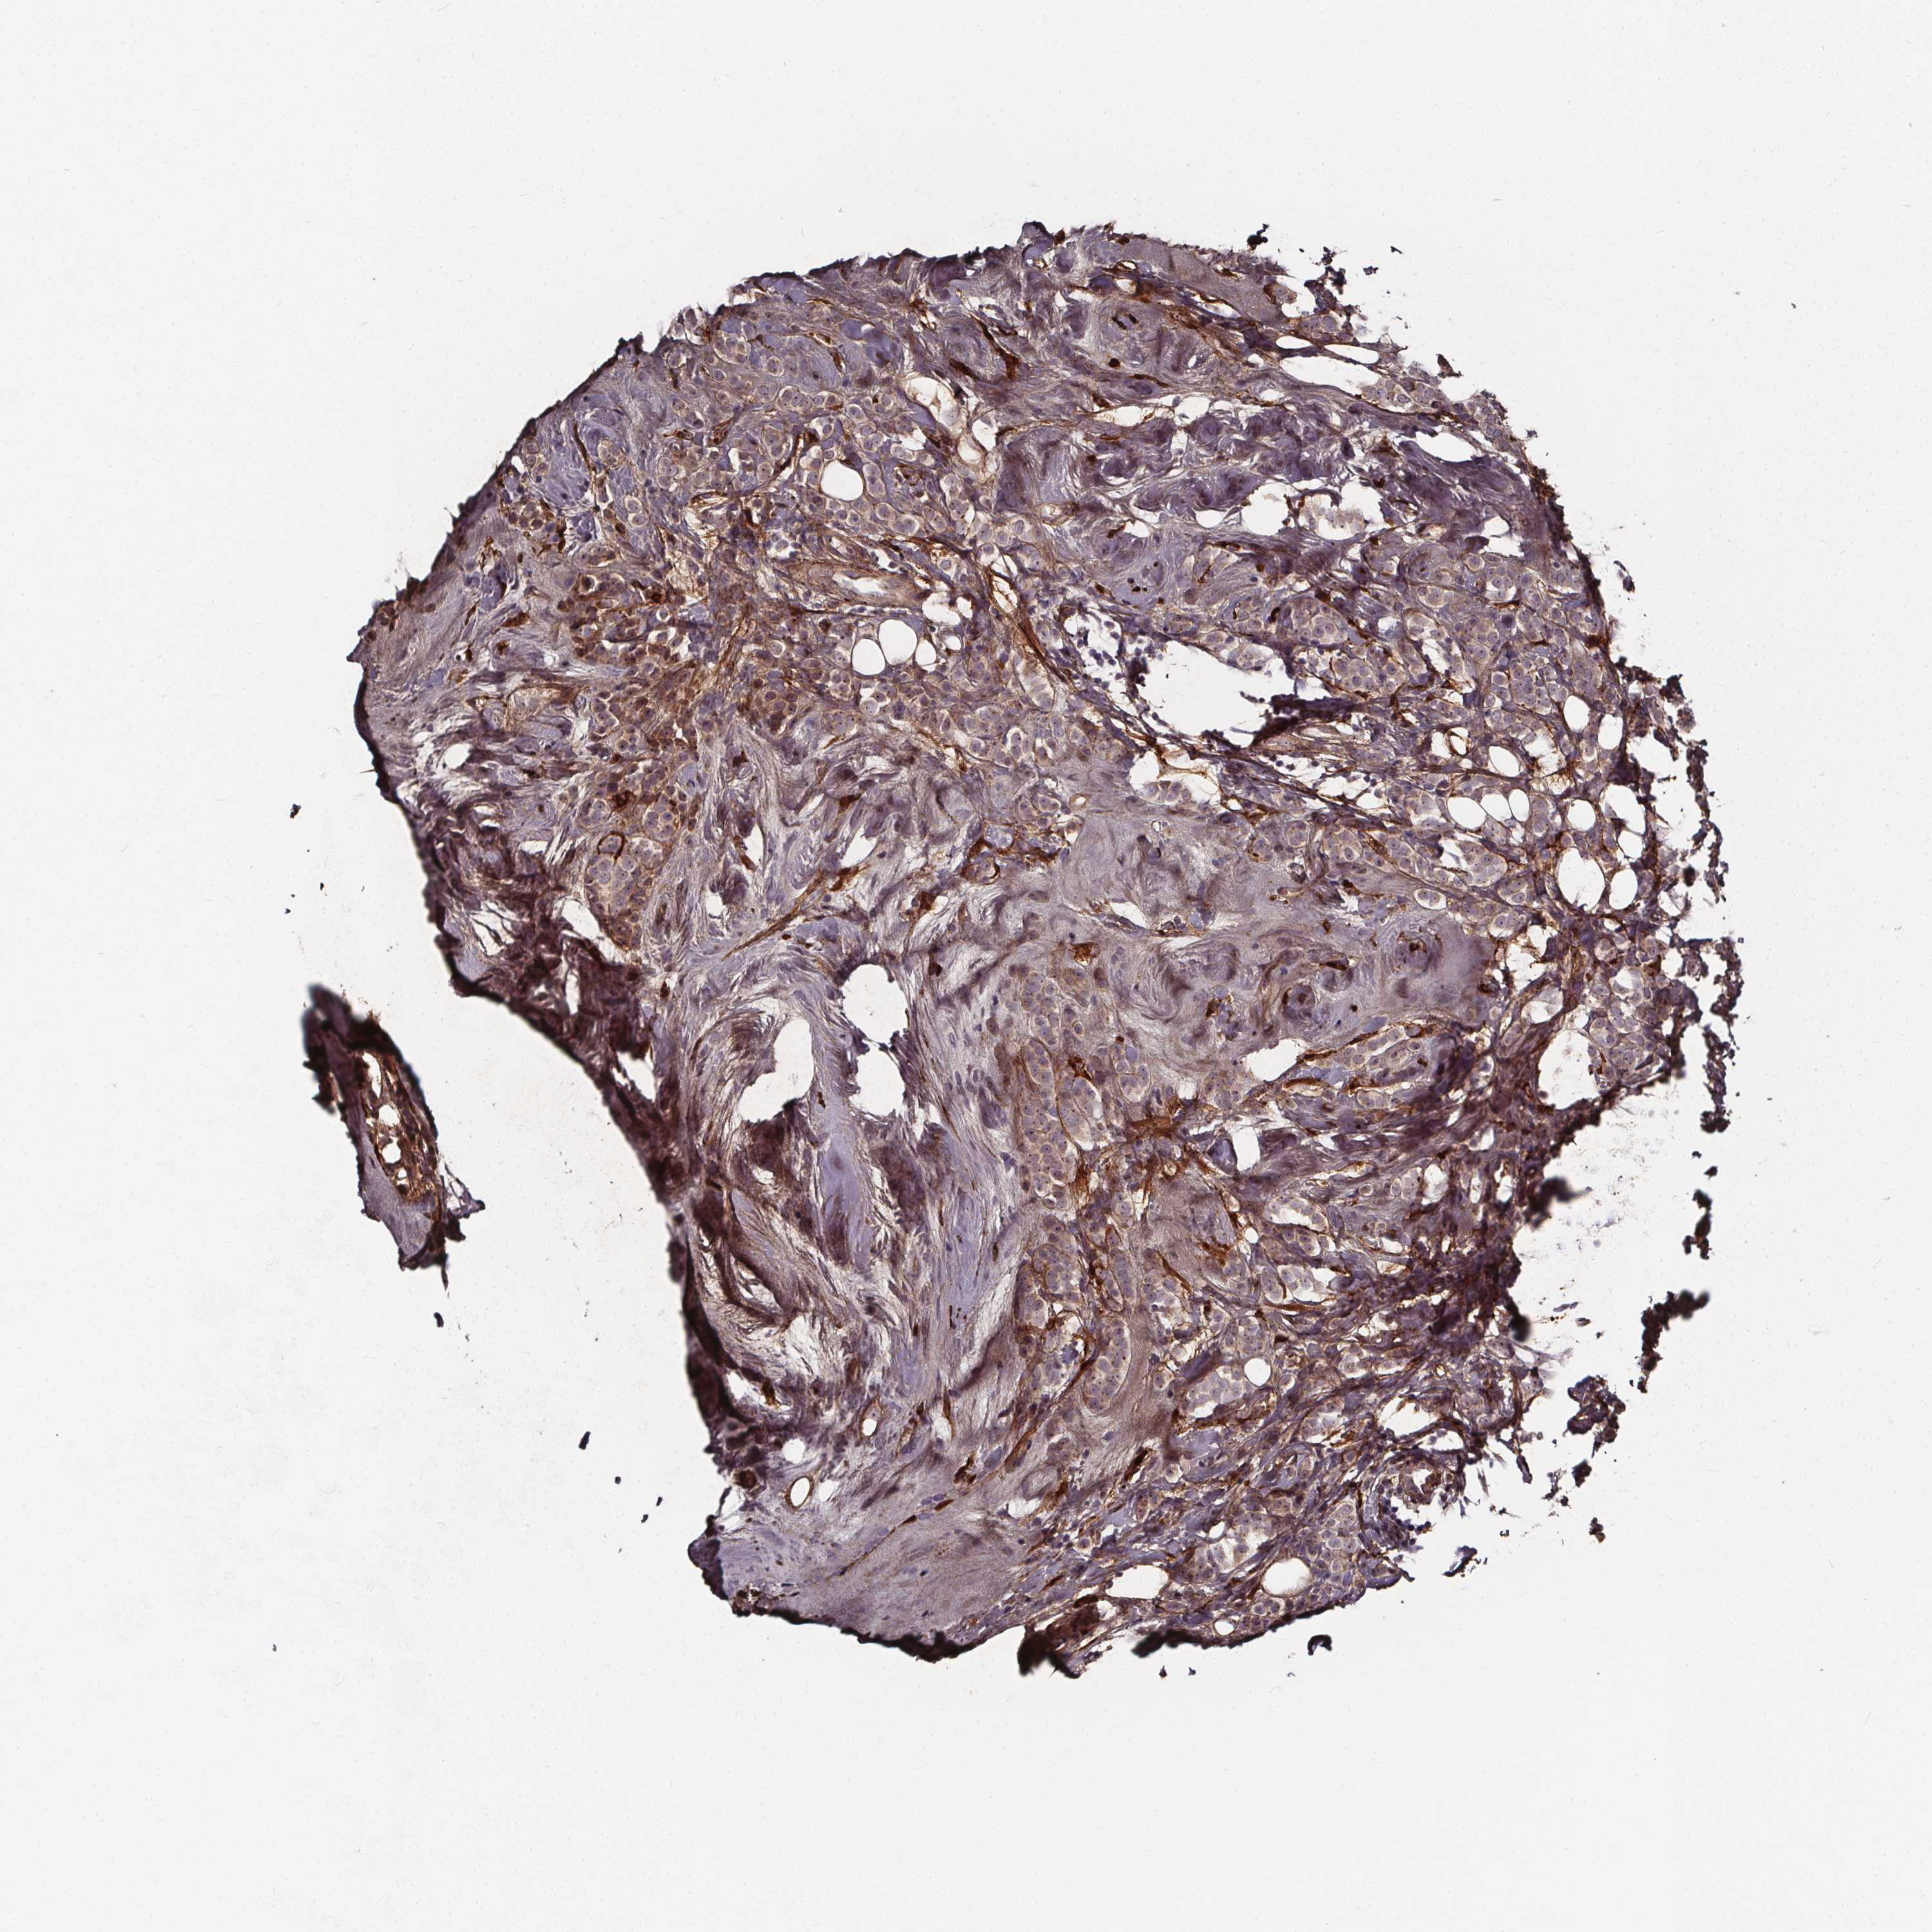

CANCER BREAST CANCER Show tissue menu

BRCA TCGA BRCA VALIDATION PROTEIN EXPRESSION